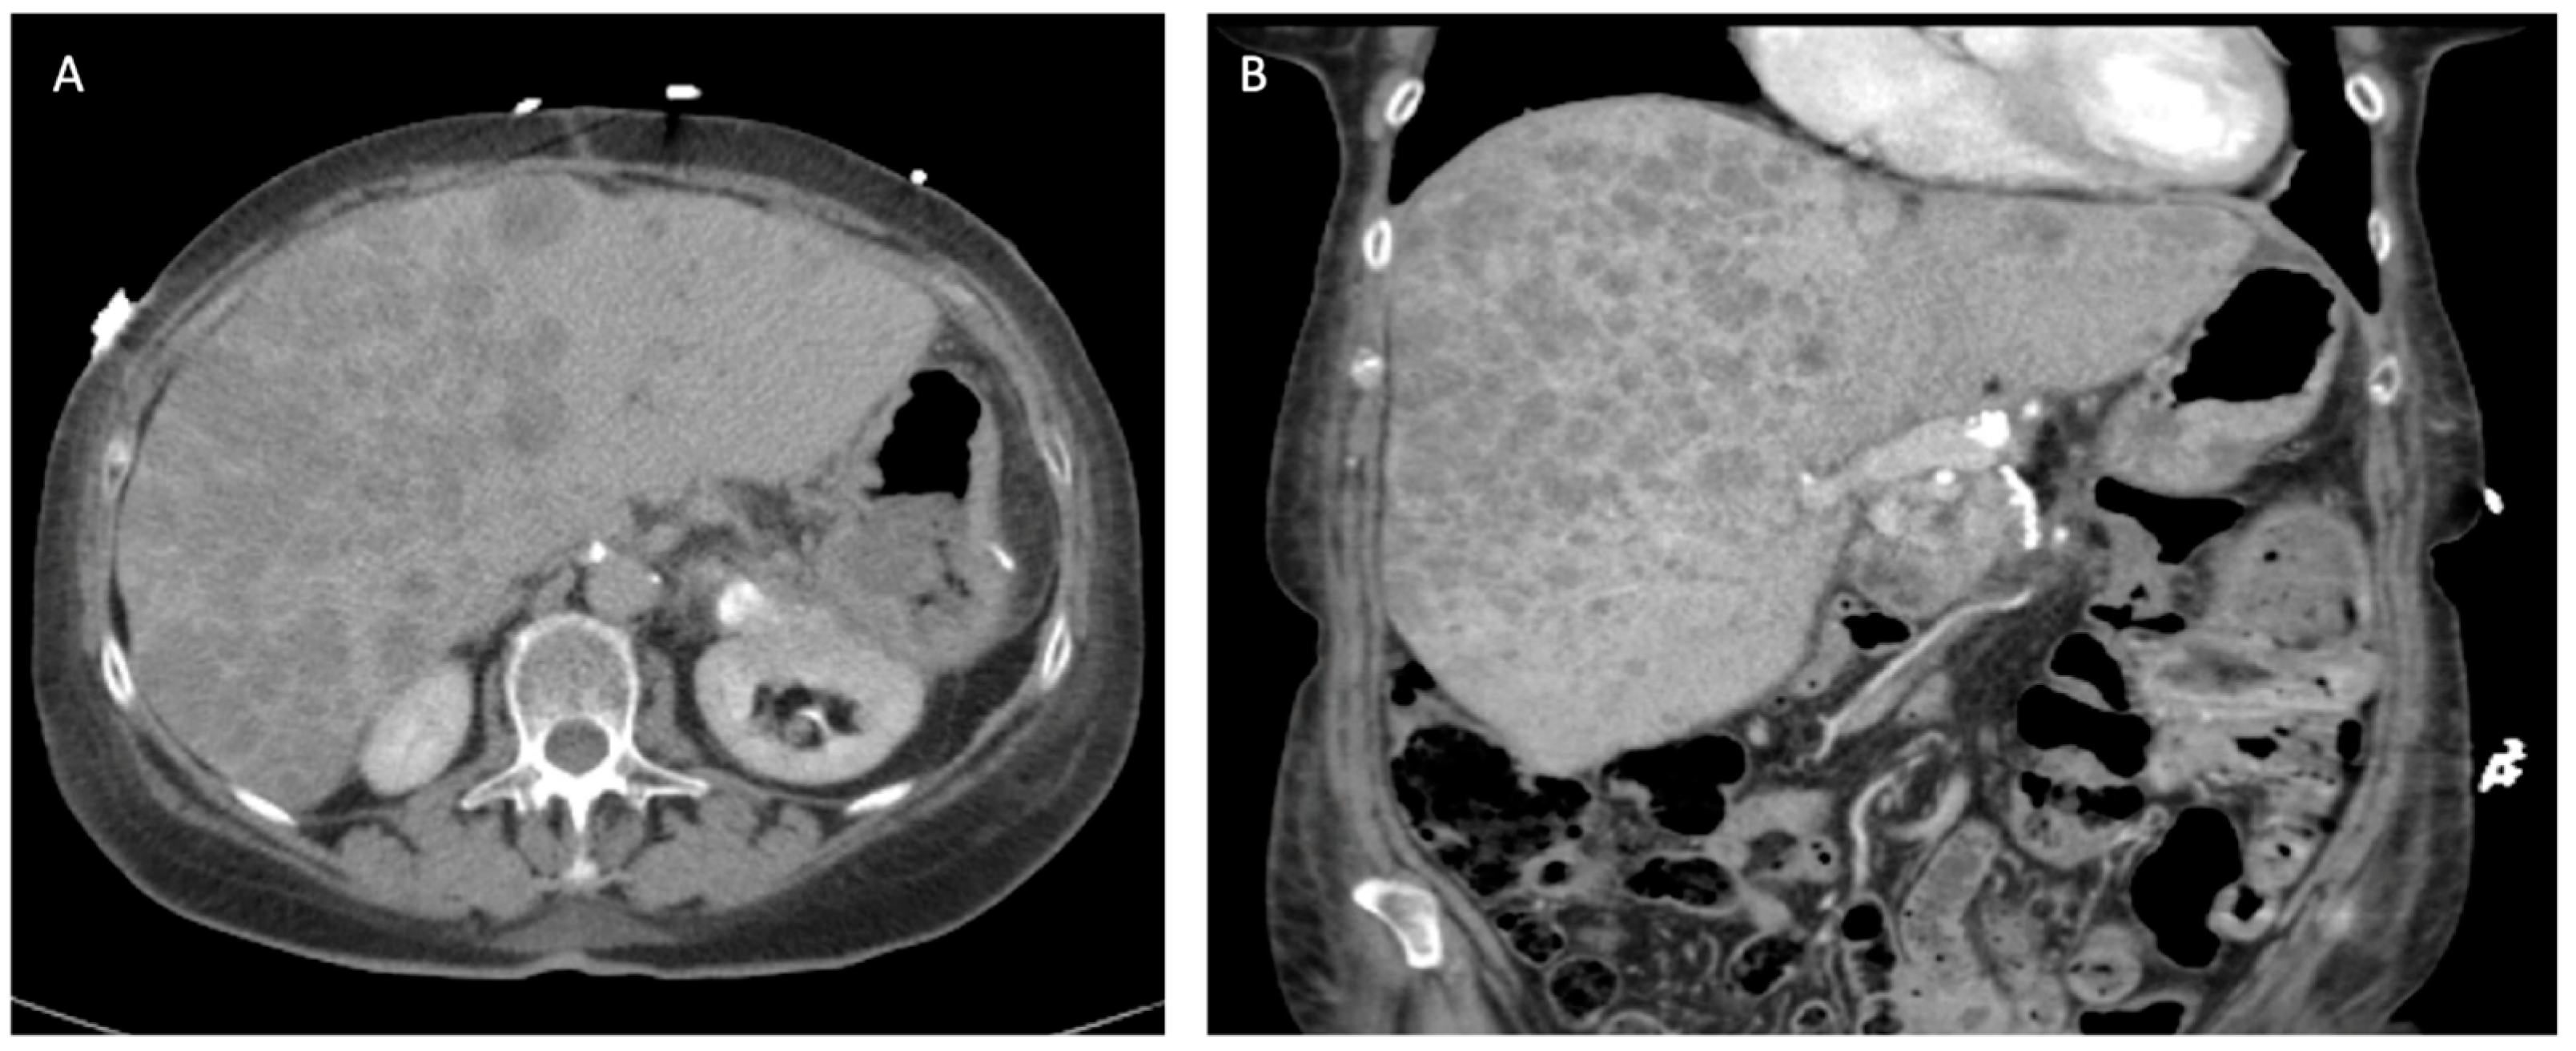

5.3.5. Tumors with Liver Metastasis

PNETs most commonly metastasize to the liver, bone, and lung. Liver metastases have been associated with worse overall survival [47]. However, curative resection can be pursued for isolated metastasis with some improvement in overall survival if the primary lesion can be resected as well [48]. The pattern of liver metastasis is usually multiple small tumors involving both hepatic lobes (Figure 6) [49]. The NANETS guidelines did not reach a consensus on the utility of cytoreduction in this setting, and the evidence supporting resection remains scarce. However, cytoreduction should be considered if patients are symptomatic and debulking is able to improve their quality of life [11]. Synchronous surgical resection of hepatic metastases and primary tumor can be performed with acceptable low mortality in selected patients [49]. Single-staged pancreaticoduodenectomy and major hepatectomy is discouraged due to its associated morbidity and mortality rates [13]. Isolated liver metastasis from neuroendocrine tumors is currently an acceptable indication for liver transplantation. The Milan or UCSF criteria should be utilized to select these patients appropriately [50]. The 5-year overall survival ranges from 36 to 90%; however, the data is not uniform and is prone to selection bias due to the retrospective nature of published studies [51,52,53].

5.3.6. Role of Liver-Directed Therapies for Liver Metastasis

Metastatic involvement of the liver significantly impacts patients’ quality of life, often leading to carcinoid syndrome, biliary obstruction, liver insufficiency, and abdominal pain (Figure 6) [54,55]. For patients experiencing symptoms but deemed not to be surgical candidates, various liver-directed therapies offer viable treatment options. These encompass percutaneous ablation techniques such as laser ablation (LA), radiofrequency ablation (RFA), microwave ablation (MWA), and irreversible electroporation (IRE). Additionally, endovascular treatments, including transarterial embolization (TAE), transarterial chemoembolization (TACE), and peptide receptor radionuclide therapy (PRRT), are also effective alternatives [51,56,57,58,59]. These modalities can be used alone or in combination with each other. In general, ablative techniques are effective and safe for oligometastatic disease. For diffuse disease with involvement of more than 75% of the liver, endovascular approaches and PRRT represent better alternatives, although they are limited by their availability at specialized centers [59].

Figure 6. Unresectable liver metastases from pancreatic neuroendocrine tumor. (A) Axial view. (B) Coronal view.